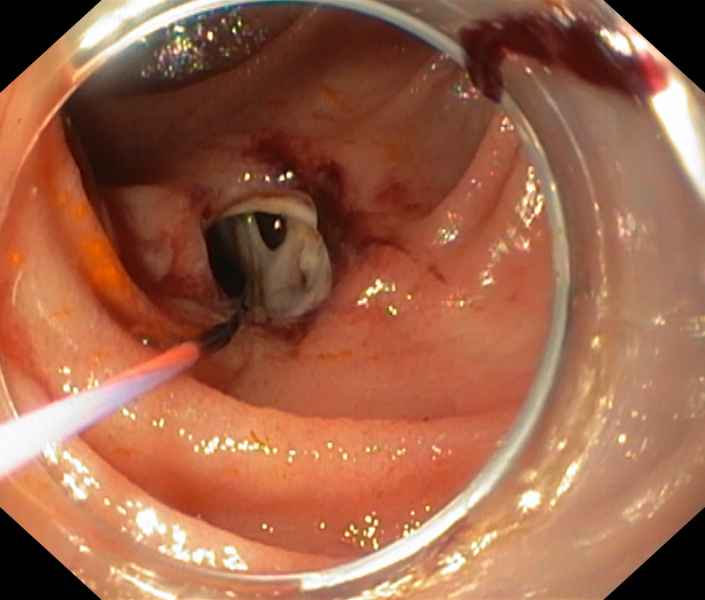

An unusual cause of upper gastrointestinal bleeding and small bowel obstruction

An unusual cause of upper gastrointestinal bleeding and small bowel obstruction

Maria Pia Costa Santos, Alexandre Ferreira, Vera Silveira, Luísa Glória, Marília Cravo

A 58-year-old black female, born in Angola, presented with melena, vomiting and a 7-year history of a right thigh mass that progressively increased in size. Her laboratory tests revealed iron deficiency anemia (hemoglobin 4.4g/dL). Computed tomography showed a large solid lesion in the right thigh, multiple smaller lesions in the lungs, pancreas and uterus, focal thickness of the small bowel wall and jejunal intussusception. Upper gastrointestinal endoscopy revealed multiple ulcerative lesions with elevated edges throughout the second and third portions of the duodenum, with 10-20 millimeters, without hemorrhagic stigmata. The histology of the duodenal and thigh lesions revealed a leiomyosarcoma.

An unusual cause of upper gastrointestinal bleeding and small bowel obstruction

Fotografia